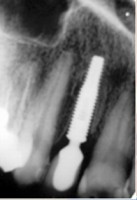

- Extração imediata

- Implante imediato

- Carga imediata